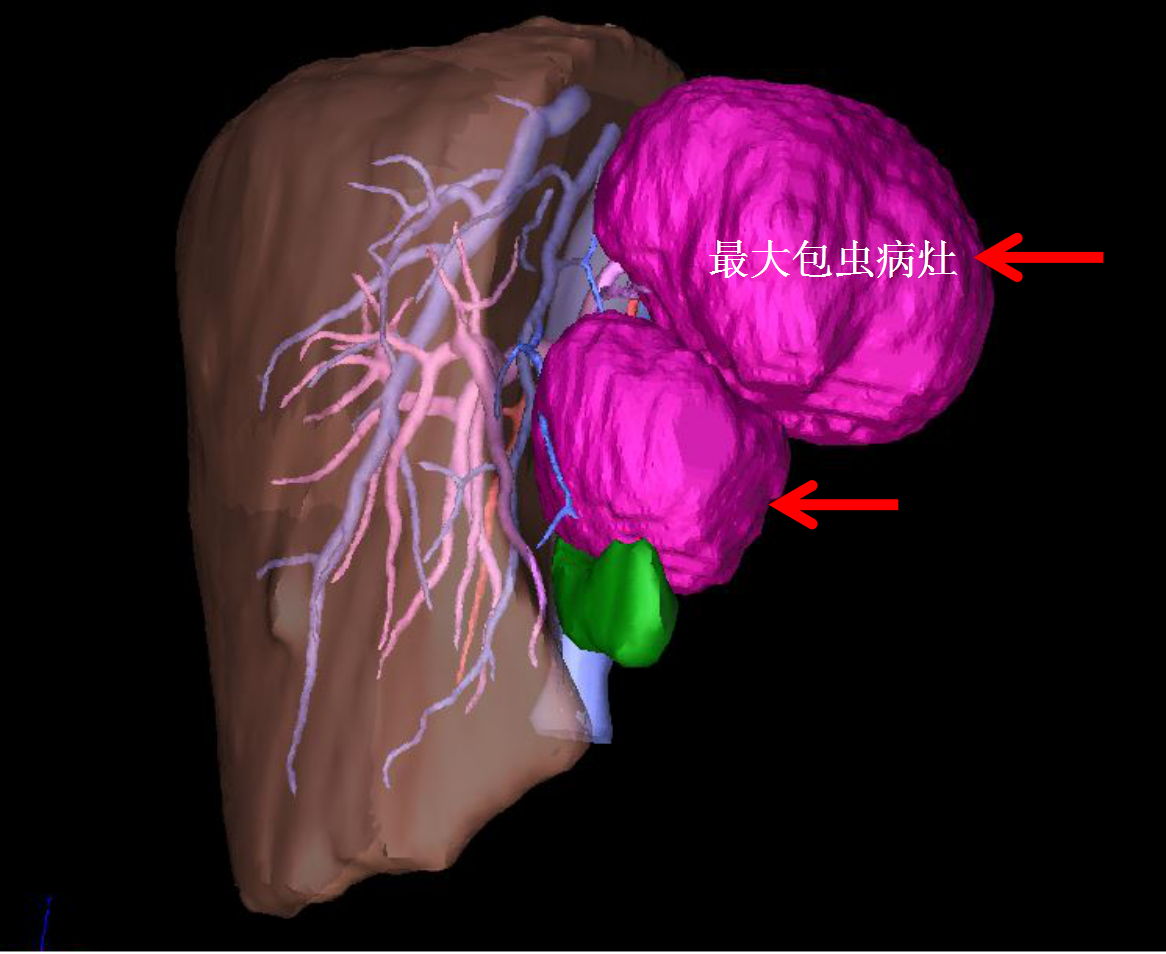

术前三维定量化手术规划及虚拟手术

经三维定量化手术评估及虚拟手术,王学栋认为,肝脏两处病灶虽然巨大,但都位于左半肝,可以挑战腹腔镜解剖性左半肝切除术。9月23日,王学栋联手拉萨市人民医院普外科平措主任等一同为小扎西实施了手术,同术前预测,由于包虫巨大导致术中肝门解剖极为困难,王学栋果断改为前入路左半肝切除术,并同时保留了肝中静脉。在该院强丹主任带领的麻醉科团队和手术室团队的保障下,手术顺利完成,出血量仅100ml。